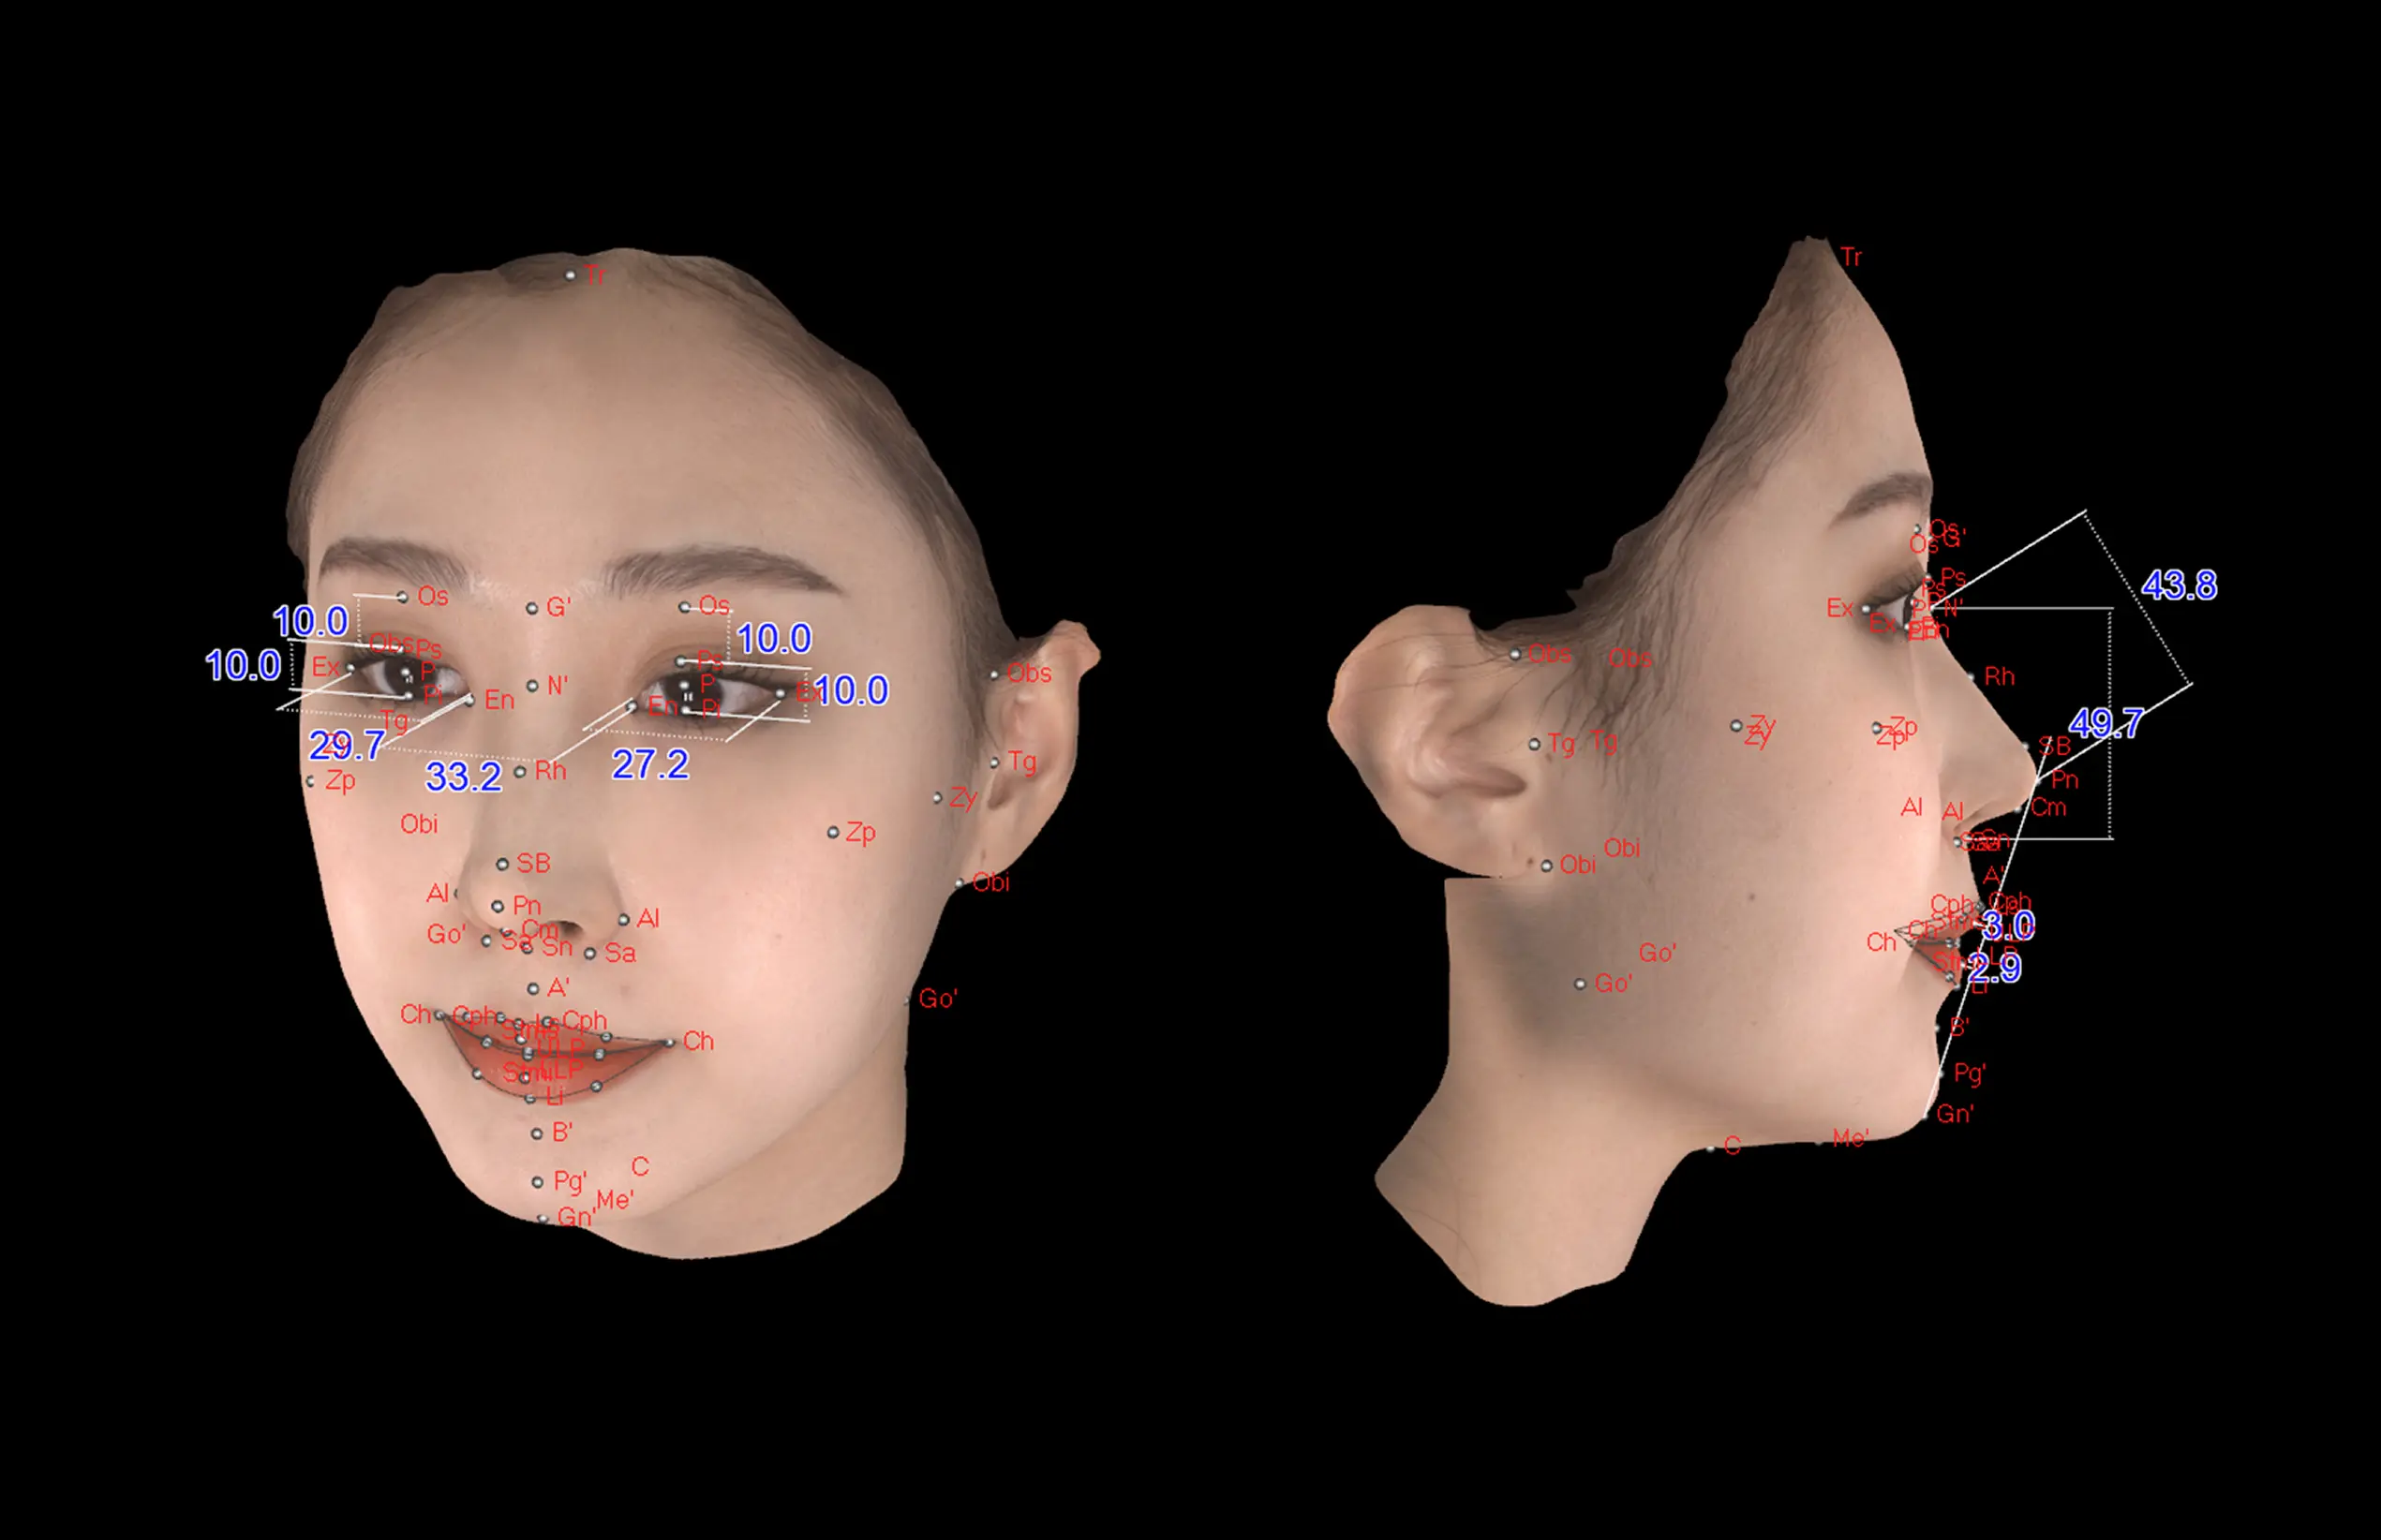

MPSPlastic surgery Solution

더보기 눈과 미간의 균형

·얼굴 상안, 중안, 하안의 직선 너비

·안각간 거리와 좌·우안 거리의 비율을 측정

하는 수평적 분석